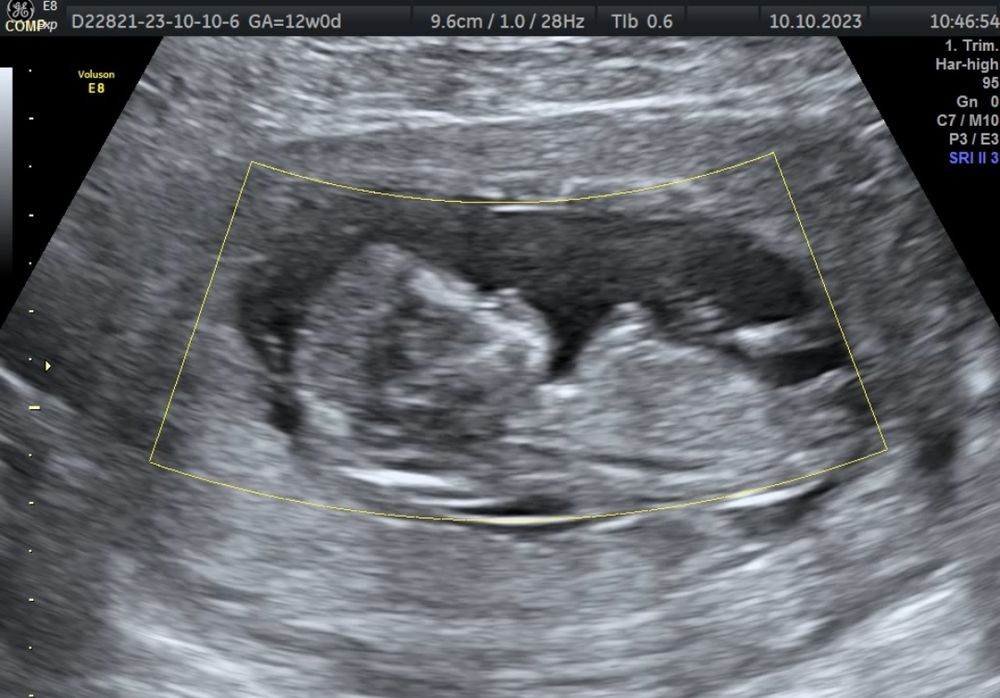

Определение пола по УЗИ в 12 недель

Девочки, пришли результаты Я в шоке. Будет сын)

Изображение Наталья , по этой схеме ориентировалась)

Ничего от мальчика не вижу) скажите потом кто)

Маргарита, пришли результаты, будет мальчик)

Вероника, половой орган смотрит к верху поэтому мальчик и форма головы)

Крис, пришли результаты. Будет мальчик)

Крис, многие видят то, что хотят видеть, как оказалось) Безусловно и мальчику рада, просто много лет представляла себе дочь)

Вероника, я была уверенна , что вот большой отросточек - ножка ) а это оказался королевский размер ))) у меня у второго сына тоже так на узи было … и в реальной жизни я очень удивилась 😅😅😅